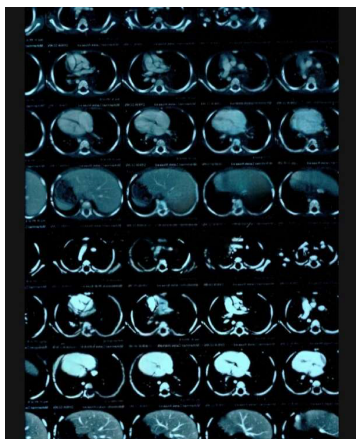

A contrast-enhanced Computer Tomography Scan of the chest showed: a large mass filling the posterior mediastinum in it's upper and middle parts, aligned with the visceral side of the right upper lobe.

MRI showed: a mass in the posterior mediastinum surrounding the tracheal branch and reaches the diaphragm, surrounding the Azygos vein, superior vena cava, aorta, major vessels and esophagus, measuring (11*5*7) cm. and foci osteolysis in the 9,11,12 thoracic vertebrae.

With an annual periodic review, for blood tests and a chest CT scan that showed a decrease in the size of the lymphangioma.

With an annual periodic review, for blood tests and a chest CT scan that showed a decrease in the size of the lymphangioma